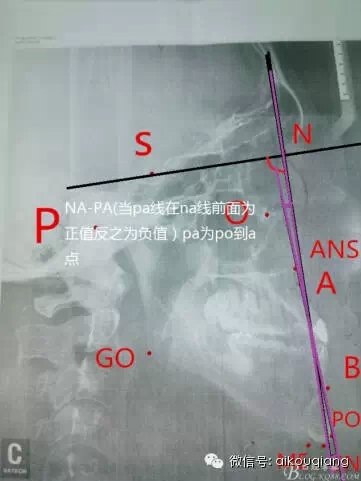

幾分鐘學(xué)會(huì)X線的測(cè)量分析圖

- 頭影測(cè)量劃線定點(diǎn)